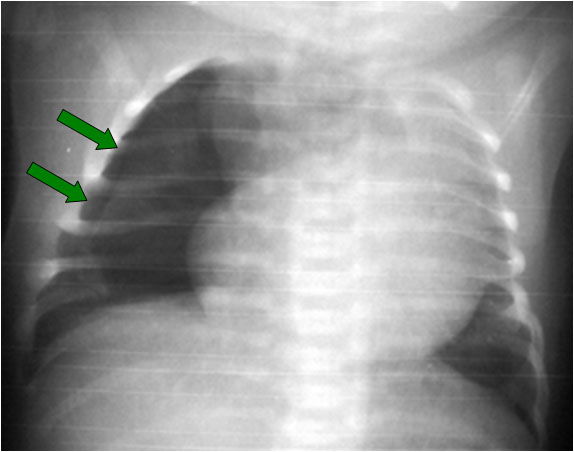

Signo de neumotórax en la radiografía anteroposterior, en decúbito supino. Un pequeño neumotórax de localización anterior puede pasar desapercibido; cuando el neumotórax perfila el surco costofrénico anterior da lugar a una imagen de doble diafragma (flechas verdes) que nos debe hacer sospechar la presencia del neumotórax.

En este caso también puede verse la línea pleural (flechas amarillas) por la extensión lateral del neumotórax. En otros pacientes, el signo del doble diafragma puede ser el único signo de neumotórax.

Este signo tiene un valor limitado, ya que las lobulaciones diafragmáticas pueden verse como doble diafragma.